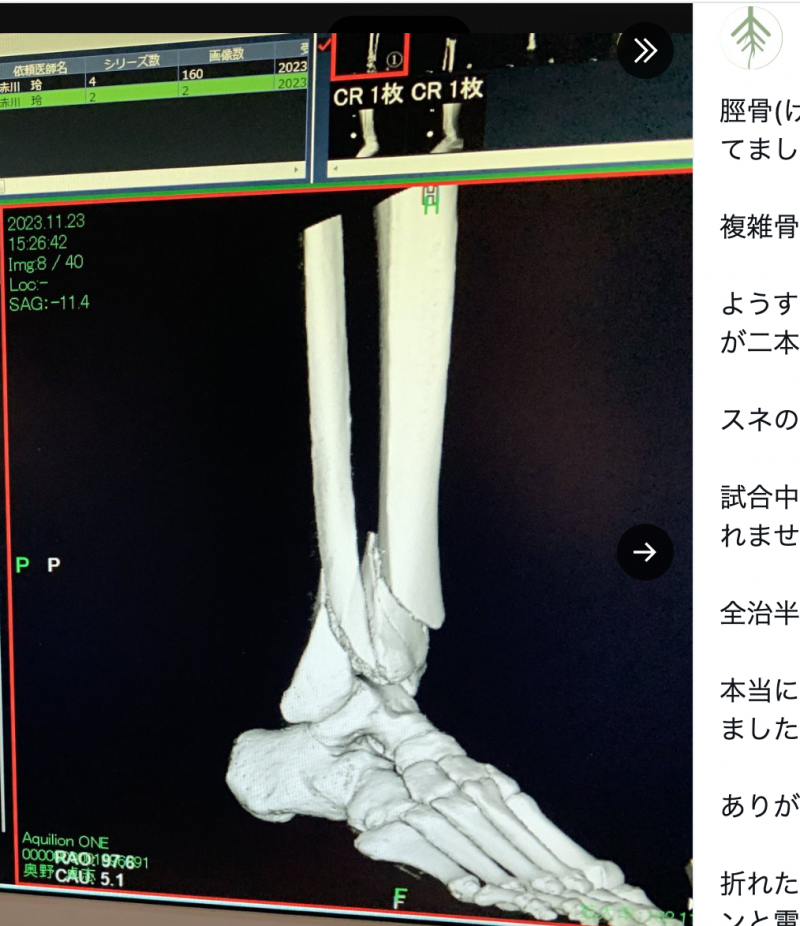

脛骨(けいこつ)と腓骨(ひこつ)両方折れた。右下に患者・奥野の名が(ごぼうの党 公式Xより)